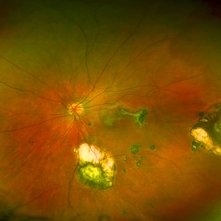

Toxoplasmosis

Toxoplasmosis

Jun 3 2017 by Gabriel Costa Andrade, PhD

Fundus photograph of an 14-year-old boy with multiple chorioretinal scars secondary to toxoplasmosis.

Photographer: Gabriel Costa de Andrade

Imaging device: Optos® California

Condition/keywords: congenital toxoplasmosis, ocular toxoplasmosis, toxoplasmosis chorioretinitis, toxoplasmosis uveitis